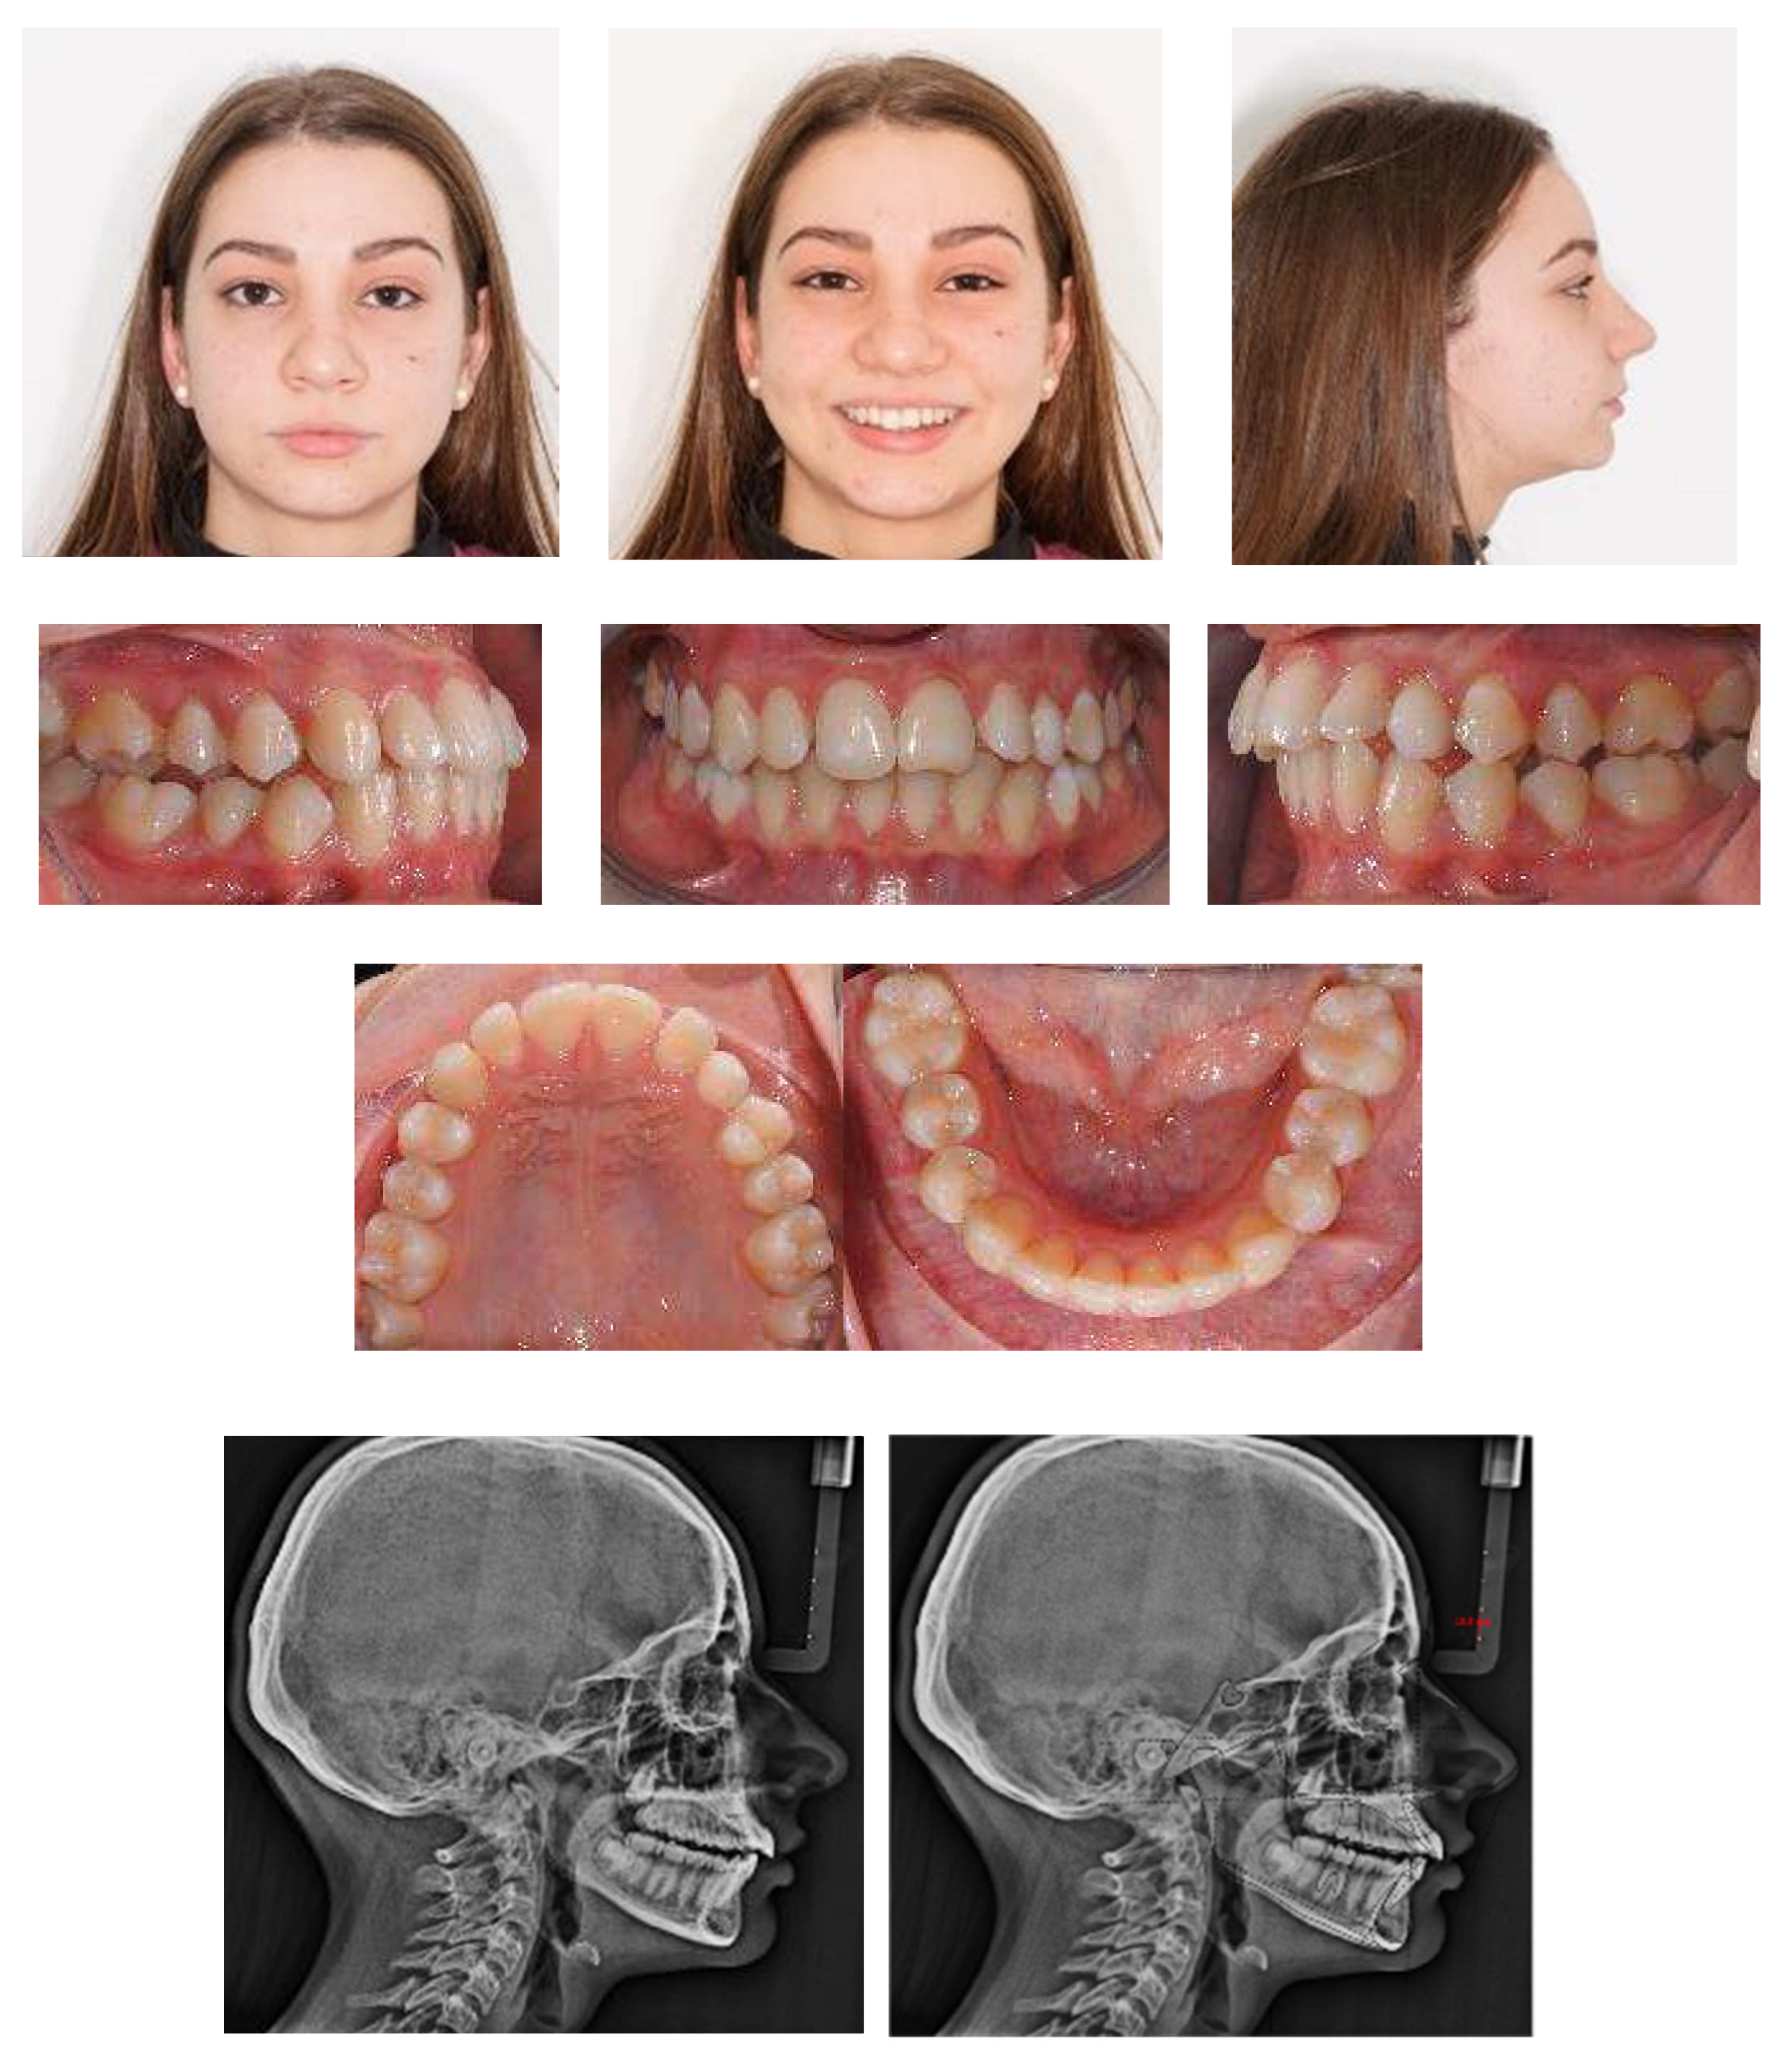

An 18-year-old female patient was referred, complaining of unpleasant smile. She presented good general health and no systemic or congenital diseases. From a frontal view, the patient presented a well-proportioned three-thirds of her face and no evidence of asymmetry. From the lateral view, the profile appeared convex with well-represented nasolabial angle, labiomental sulcus, and lip competence. Intraorally, the patient showed a Class II malocclusion with the molar Class I relationship, edge to edge canine relationship on both sides, increased overjet, overbite, and the retention of the 63. Panoramic, lateral headfilm, and dental cast records were taken (Figure 11).

Figure 11.

An 18-year-old female with dentoskeletal Class II with impacted upper left canine before treatment.

The initial cephalometric analysis showed a skeletal Class I relationship (ANB, +2.6°) and mesodivergent pattern with the proclination of the upper (I/ANS-PNS 118.8°) and lower (i/GoGn:102.2°) incisors. All the radiographic findings, the age of the patient, the prolonged deciduous retention, and the risk of root resorption of the adjacent tooth, led clinicians to conclude that the permanent canine would not erupt properly without intervention (Table 2).

The position of the impacted canine showed an alpha angle of 58° and the Ericson and Kurol II sector classification. No clinical symptoms on articular examination were detected (Figure 12).